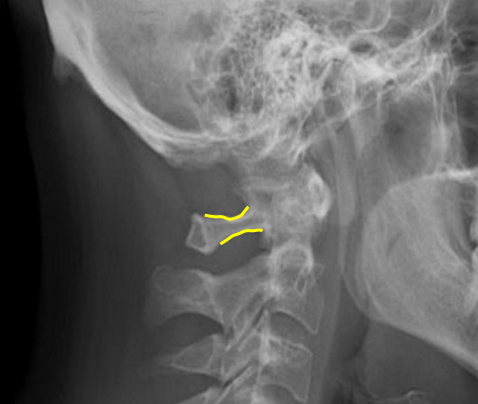

Junction of laminae

Pedicle shadows

Vertebral waist